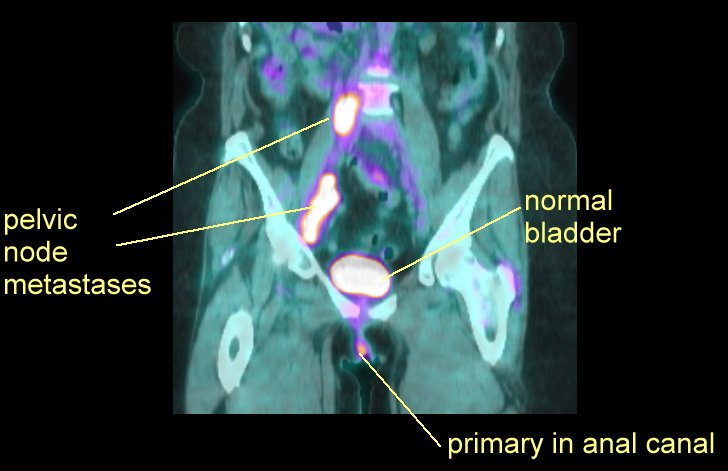

anatomy images (here, here, here, here, here, male, female) PET scans are very good at showing the cancer and particularly the lymph node spread (here, here, here, here, here)